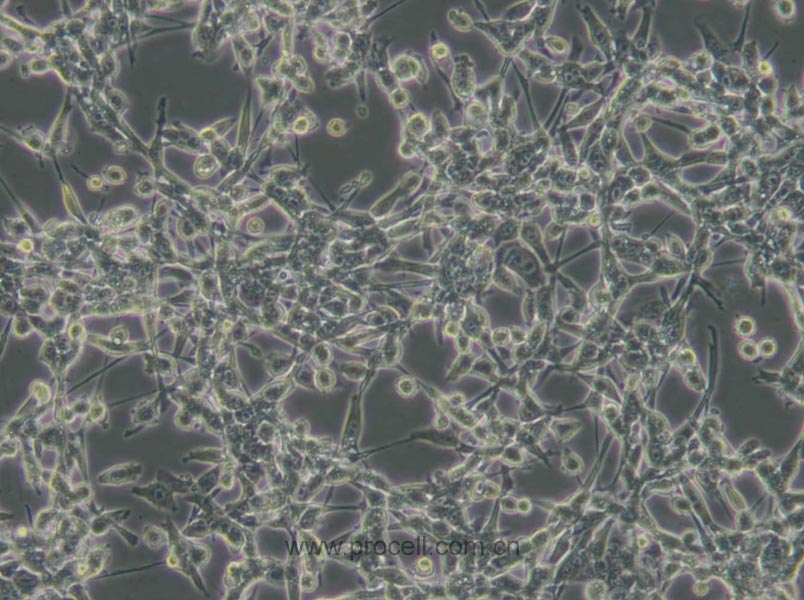

| 生長特性 | 貼壁細胞 |

| 細胞形態(tài) | 成纖維細胞樣 |